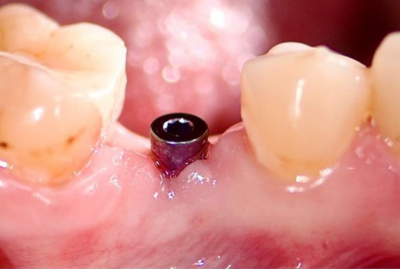

КЛинический случай максима хышова

Удаление зуба 26. Установка имплантатов VEGA+ в позиции 25 и 27.

✔️ В позицию зуба 27 установлен VEGA+ RV 4.6x10 mm. Получена первичная стабильность 20 Н/см. Установлен винт-заглушка

✔️В позицию зуба 25 установлен VEGA+ RV 4.1x14 mm. Получена первичная стабильность 50 Н/см. Установлен винт-заглушка.